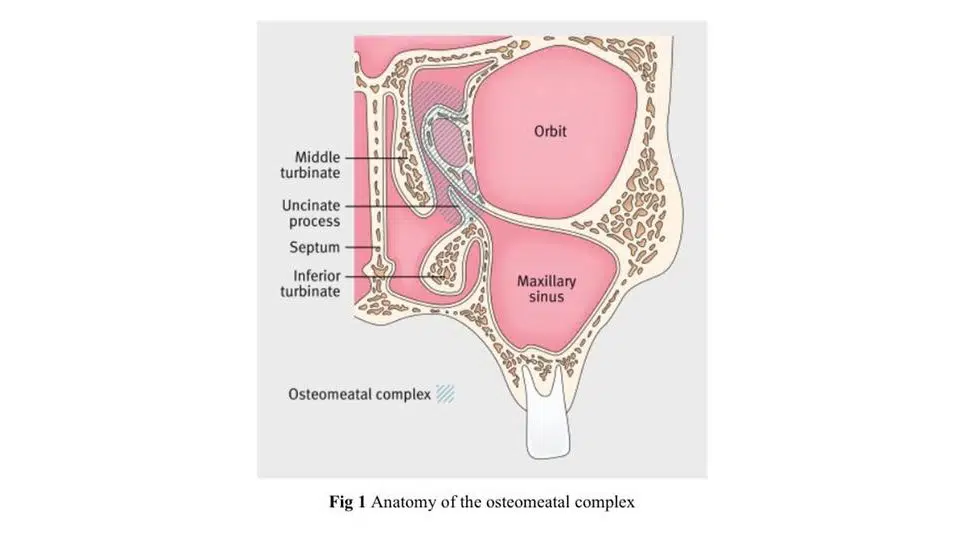

- ناهنجاری کمپلکس استئوماتال

به نظر می رسد عامل تحریک کننده در سینوزیت حاد انسداد دهانه سینوس است، به طور معمول دهانه سینوس ماگزیلاری در زیر توربین میانی است (شکل ۱).